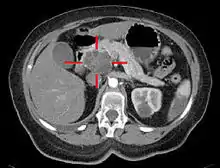

胰臟癌可借助電腦斷層(CT)或內視鏡超音波(EUS)等醫學影像技術確診,並協助判斷腫瘤是否能以外科手術切除[11]。在配合顯影劑使用的電腦斷層掃描中,胰臟癌會慢慢的吸收顯影劑,而正常的胰臟組織則會將顯影劑快速排除,慢性胰臟炎排除顯影劑的速度則較慢[55]。核磁共振和正子電腦斷層掃描也可用來診斷胰臟癌[2];在某些案例中,核磁共振膽胰管攝影術也很有用[37]。 腹部超音波的敏感度較低,可能會遺漏較小的腫瘤,但能協助診斷散播到肝臟或腹水中的腫瘤[11];由於腹部超音波便宜又快速,在做其他檢查前也能以此做初步的檢查[56]。